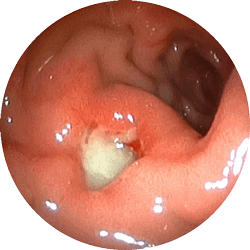

胃潰瘍2

胃潰瘍

心窩部の重い感じで来院

内服薬1ヶ月で治癒